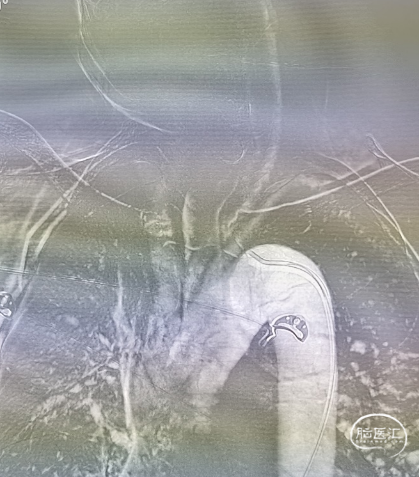

DSA(外院)

左侧椎动脉V4段狭窄,远端见瘤样扩张;右侧椎动脉闭塞。脑血管符合硬化表现。(阅片)

造影提示右侧椎动脉闭塞,左侧椎动脉V4多发重度狭窄,并V4段夹层动脉瘤